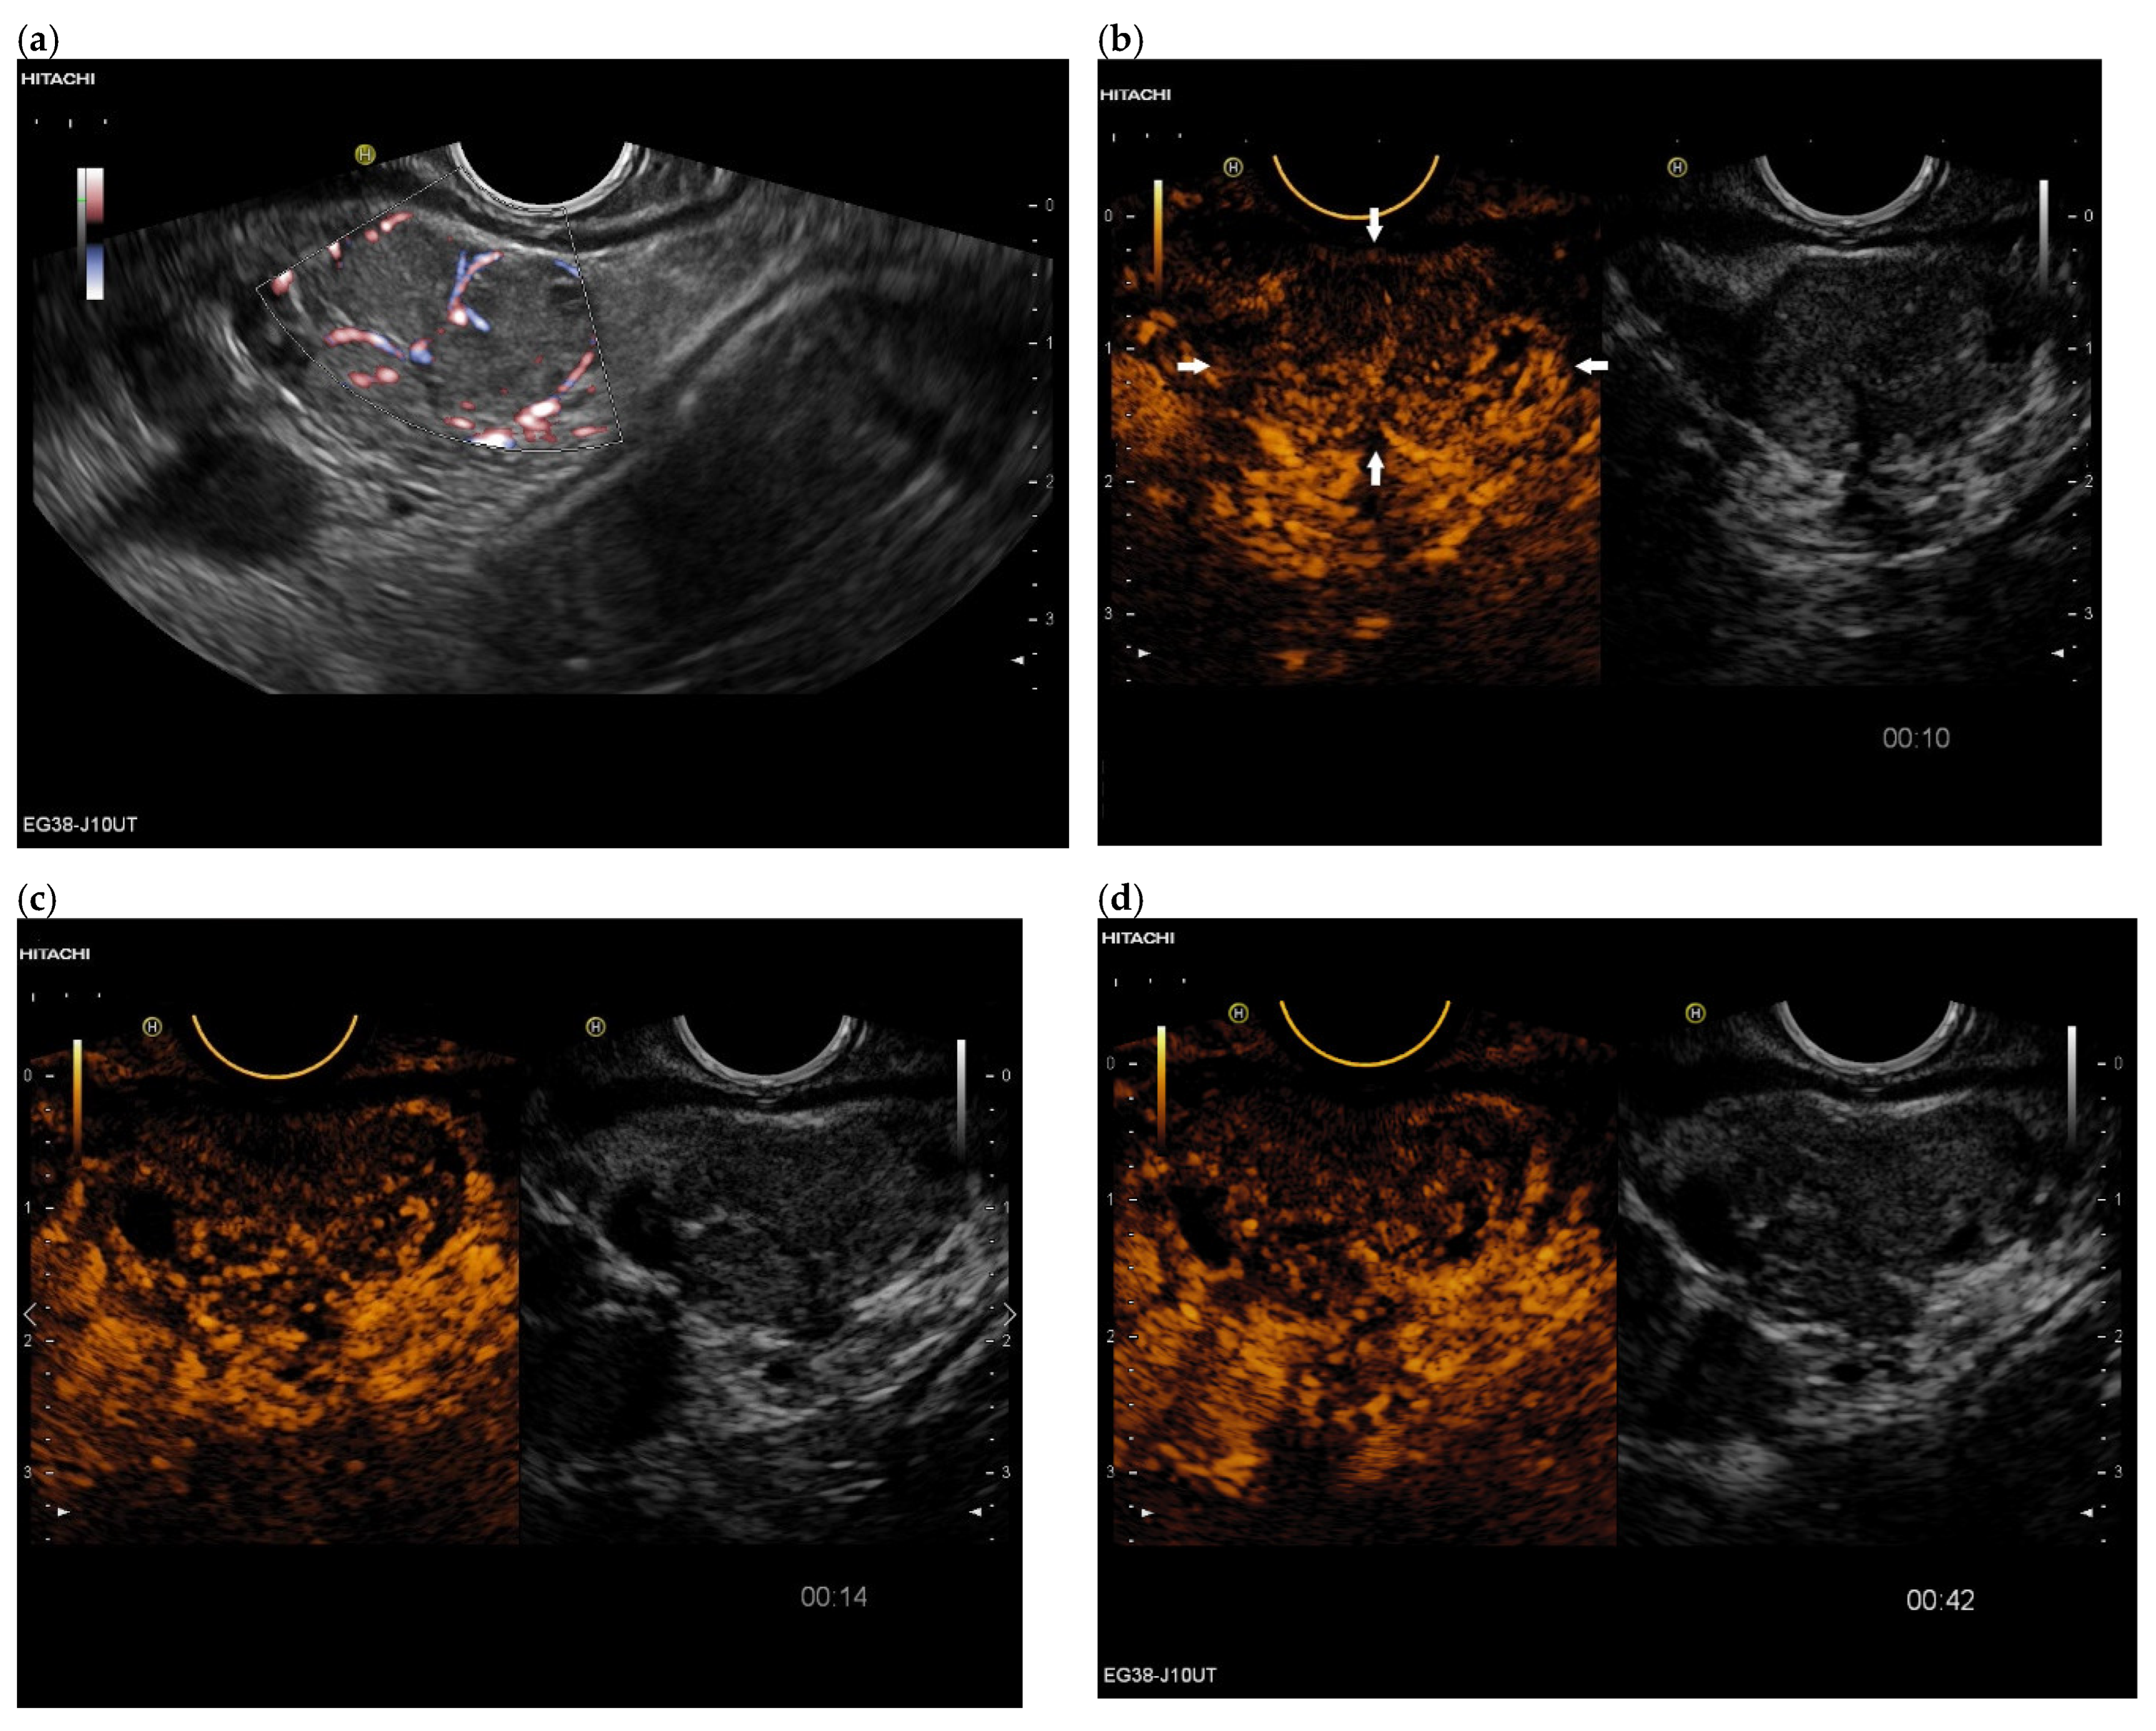

3.4. CEUS and CH-EUS

| Colour Doppler Imaging | RCC metastases are hypervascularized Most other pancreatic metastases are hypovascularized | No hypervascularization | Hypervascularized |

| RCC metastases [83] (n = 4) | Hyperenhancement, Early | Hyperenhancement | ||

| RCC metastases [61] (n = 3) | Hyperenhancement, homogeneous pattern | Slow washout | ||

| RCC metastasis [86] (n = 1) | Hyperenhancement, Inhomogeneous pattern | No washout | ||